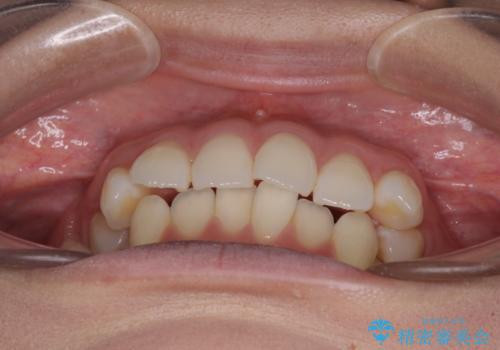

前歯のデコボコを解消 インビザラインの矯正治療

- 前歯のデコボコを治したいとのことで来院された患者様です。

上下顎ともに歯列全体の後方移動とIPR(歯と歯の間を削る)によってデコボコが解消するように設計し、インビザラインにより治療を行うこととしました。